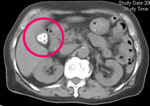

腹部CT

各臓器の形態がよくわかります。内臓脂肪の正確な計測もできます。

胆石

本人は右上腹部にときどき差し込むような痛みを自覚していた。

脂肪肝(○)と内臓脂肪の増加(矢印)

血液検査で中性脂肪が高く、腹囲が85cmを越えている。